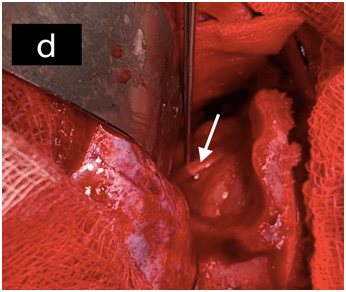

The patient underwent surgery via a right fronto orbital approach. He was anesthetized via an orotrachealroute, and was positioned supine with the neck flexed 30 degrees in a neutral position (Figure 4A &4B).After frontoorbitotomy, and dissection of orbital fat, an opaque cystic lesion was found in the intraconoalspace, which was densely adherent to surrounding tissues(Figure 4C & 4D).

Removal was not possible because of the adherence to the neighbouring structures. First a puncture of the cyst and an aspiration with a syringe was done, and a transparent clear fluid was aspirated which is characteristic for hydatid cyst, then a microscopic extirpation of the cystic membrane, combined with abundant washing of the site of operation was washed with hypertonic saline solution.We found two others cystic membranes that we removed (Figure 4E & 4F).